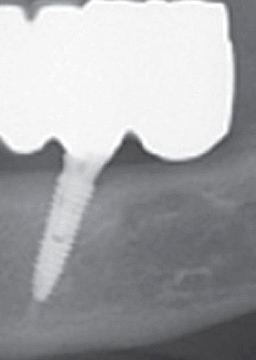

하지만 풀아치임플란트 시술은 기존 임플란트 치료와는 그 차이가 확연하게 나다 보니, 무치악 환자분들께서 선호하는 임플란트 시술이라고 하였어요. 이는 상악 하악에 각각 4개에서 6개까지만 임플란트를 식립하다 보니, 경제적인 측면에서 훨씬 부담이 덜할 수 있는 임플란트 시술이라고 하였어요. 이렇게 임플란트 시술을 한 후에 하나의 보철물을 이에 연결하다 보니 전체 치아의 저작기능이 회복할 수 있다고 하였어요.

풀아치임플란트 시술이란 상악 하악에 각각 4개에서 6개까지 인공 치근을 심어 잇몸뼈에 심은 후에 하나로 연결된 보철물을 임플란트에 고정하는 시술을 말하였어요. 이러한 풀아치 임플란트 치료는 발치부터 임플란트 시술, 보철물 장착까지 전 과정을 3D CT와 같은 디지털 시스템에 기반하다 보니 무절개 수술이 가능할 수 있었어요. 이러한 풀아치임플란트 시술은 기존 임플란트에 비하여 식립 개수가 절반 정도이다 보니 경제적인 부담이 줄어들 수 있었어요.

또한 뼈 이식 없이 남아 있는 건강한 잇몸 뼈를 이용하여 수술이 가능해지며, 이로 인하여 잃어버렸던 저작기능을 회복할 수 있기에 기능적인 측면에서도 큰 기대효과를 볼 수 있었어요. 게다가 인공치근 개수가 적다 보니 잇몸 절개로 인해 발생된 출혈을 줄일 수 있었으며, 수술 시간 및 회복 기간이 짧다 보니 전체적인 치료 기간이 일반 임플란트 치료에 비하여 짧을 수 있었어요.